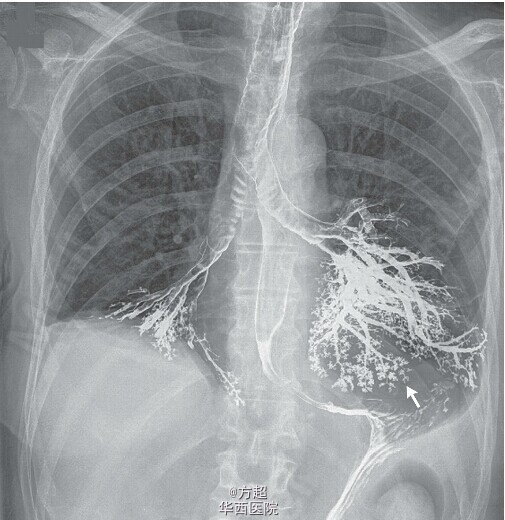

老年患者,因体重下降、吞咽困难就诊,并安排行消化道钡剂造影检查,在检查期间并未出现呛咳等不适,检查结束后不久即出现进行性加重低氧性呼吸衰竭,立即予以气管插管等抢救;并转入 ICU进一步,床旁胸部 X 线检查显示其左、右主支气管内均有钡剂存在,且基本显示出了支气管的轮廓,双肺下叶基底段支气管,左肺上、下叶的肺段支气管,均清晰显影,同时可见钡剂也蔓延到了其较小的气道,并显示出树芽状的影像;支气管镜检证实患者的左、右肺下叶和舌叶均有钡剂存在,并吸出了大量钡剂。随即患者出现休克,并于心脏骤停后发生严重的缺氧性脑损伤,尽管经过心肺复苏,液体复苏、应用正性肌力药和抗生素等紧急治疗,患者病情仍继续恶化。最终患者家属选择了保守的姑息治疗,患者于不久后去世。Mazen Albeldawi, M.D., and Rohit Makkar, M.D.N Engl J Med 2012; 366:1038;全文链接:http://www.nejm.org/doi/full/10.1056/NEJMicm1108468;消化道钡剂造影目前仍为临床常用检查,虽然钡剂误吸等发生较少,但仍需引起重视,必要的风险告知,及时有效的抢救应对都很关键